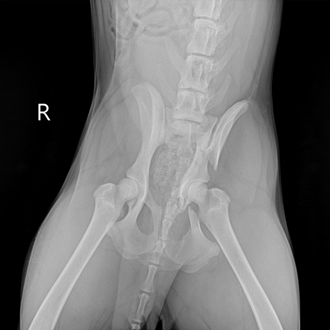

외상 응급

(교통사고)

출혈, 장기 손상, 골절 등 복합 손상이 동반될 수 있습니다.

전신 상태 평가 후 단계적인 치료 계획이 필요합니다.